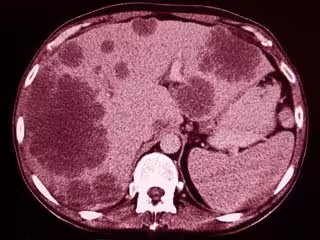

Archivo - Liver tumors -CT

Archivo - Liver tumors -CT - GETTY IMAGES/ISTOCKPHOTO / SEMNIC - Archivo